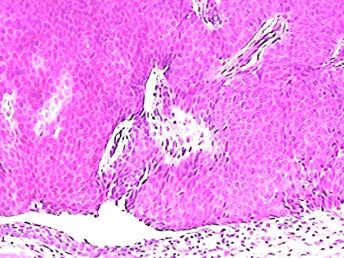

Nuestro equipo médico cuenta con experiencia probada en el análisis macroscópico y microscópico de (biopsias y resecciones) de cualquier origen. Entregamos información completa y consiente de una gama muy extensa de patologías, así como los diagnósticos y pronósticos a médicos y pacientes.

Inmunohistoquímica

Realizamos tinciones para múltiples marcadores que cubren varios propósitos, incluidos la identificación y clasificación de los neoplasmas. Para ello, se procede determinando el perfil receptor de las células cancerígenas y otras anormalidades de la señalización de dichas células que representan objetivos para la terapia.